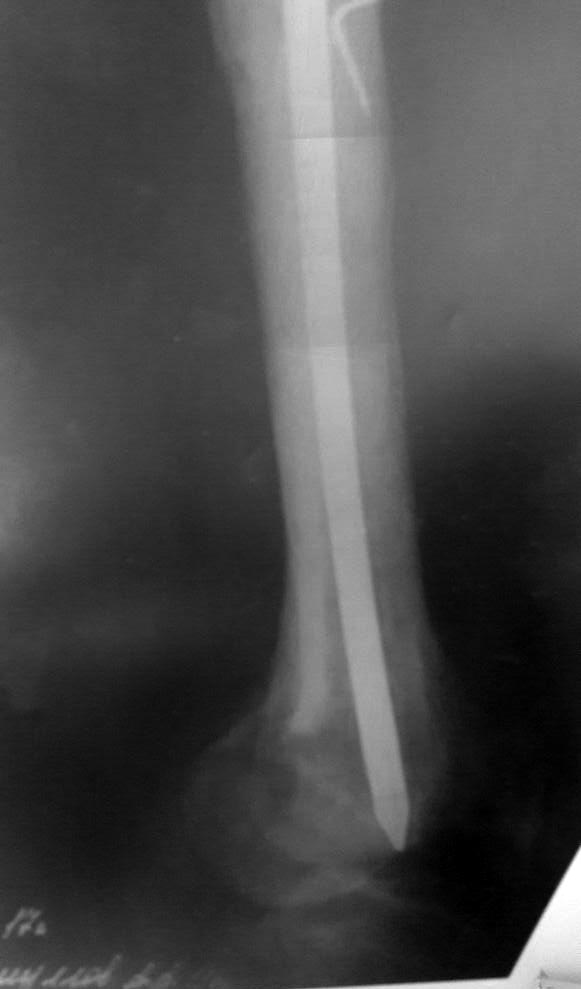

Доброго дня коллеги!поступает пациент, оперирован 9 лет назад, последний месяц начали беспокоить боли в коленном суставе при ходьбе

Визуально отек коленного сустава, синовит, ограничение и сгибания и разгибания. наш план зайти антеградно при помощи эопа и все-таки попытаться его удалить. Сейчас ищем инструмент через Москву. на потоке это никогда не ставили. Хотелось бы услышать мнения, советы.